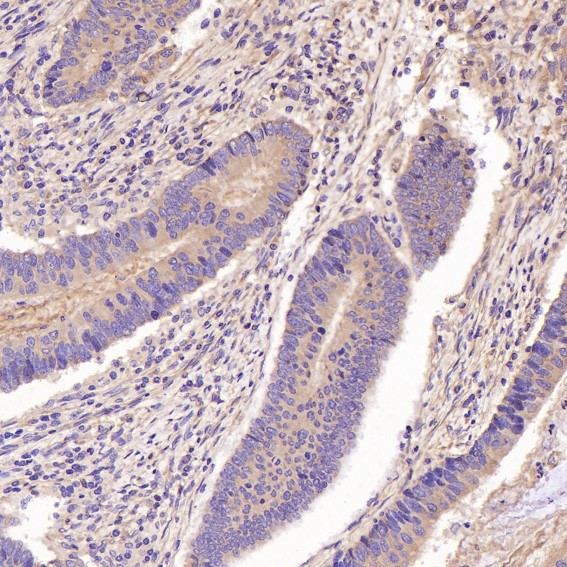

Immunohistochemical analysis of paraffin-embedded human colon carcinome, using GSK3 beta Antibody.

Immunohistochemical analysis of paraffin-embedded Human colon cancer, using the Antibody.

Immunohistochemical analysis of paraffin-embedded human colon carcinome, using GSK3 beta Antibody.

Immunohistochemical analysis of paraffin-embedded Human colon cancer, using the Antibody.